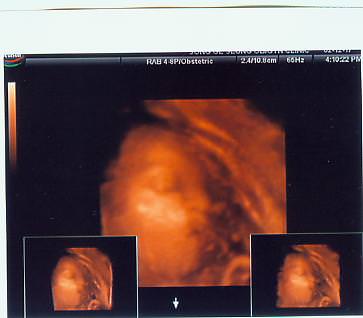

ㅎㅎ 진주가 놀래지나 않을지 모르겠네

먼저 진주한테 허락도 받지 않고 이렇게 사진을 옮겨다 놓았어.

게시판에 진주사진이 있는데 못보신분들도 있을것 같고해서. 이웃집 사진관으로 옮기게 되었어.

진주야~~~ 미안~~~ 어때요

진주 정말 마음씨만큼 이쁘고 착하게 생겼죠?